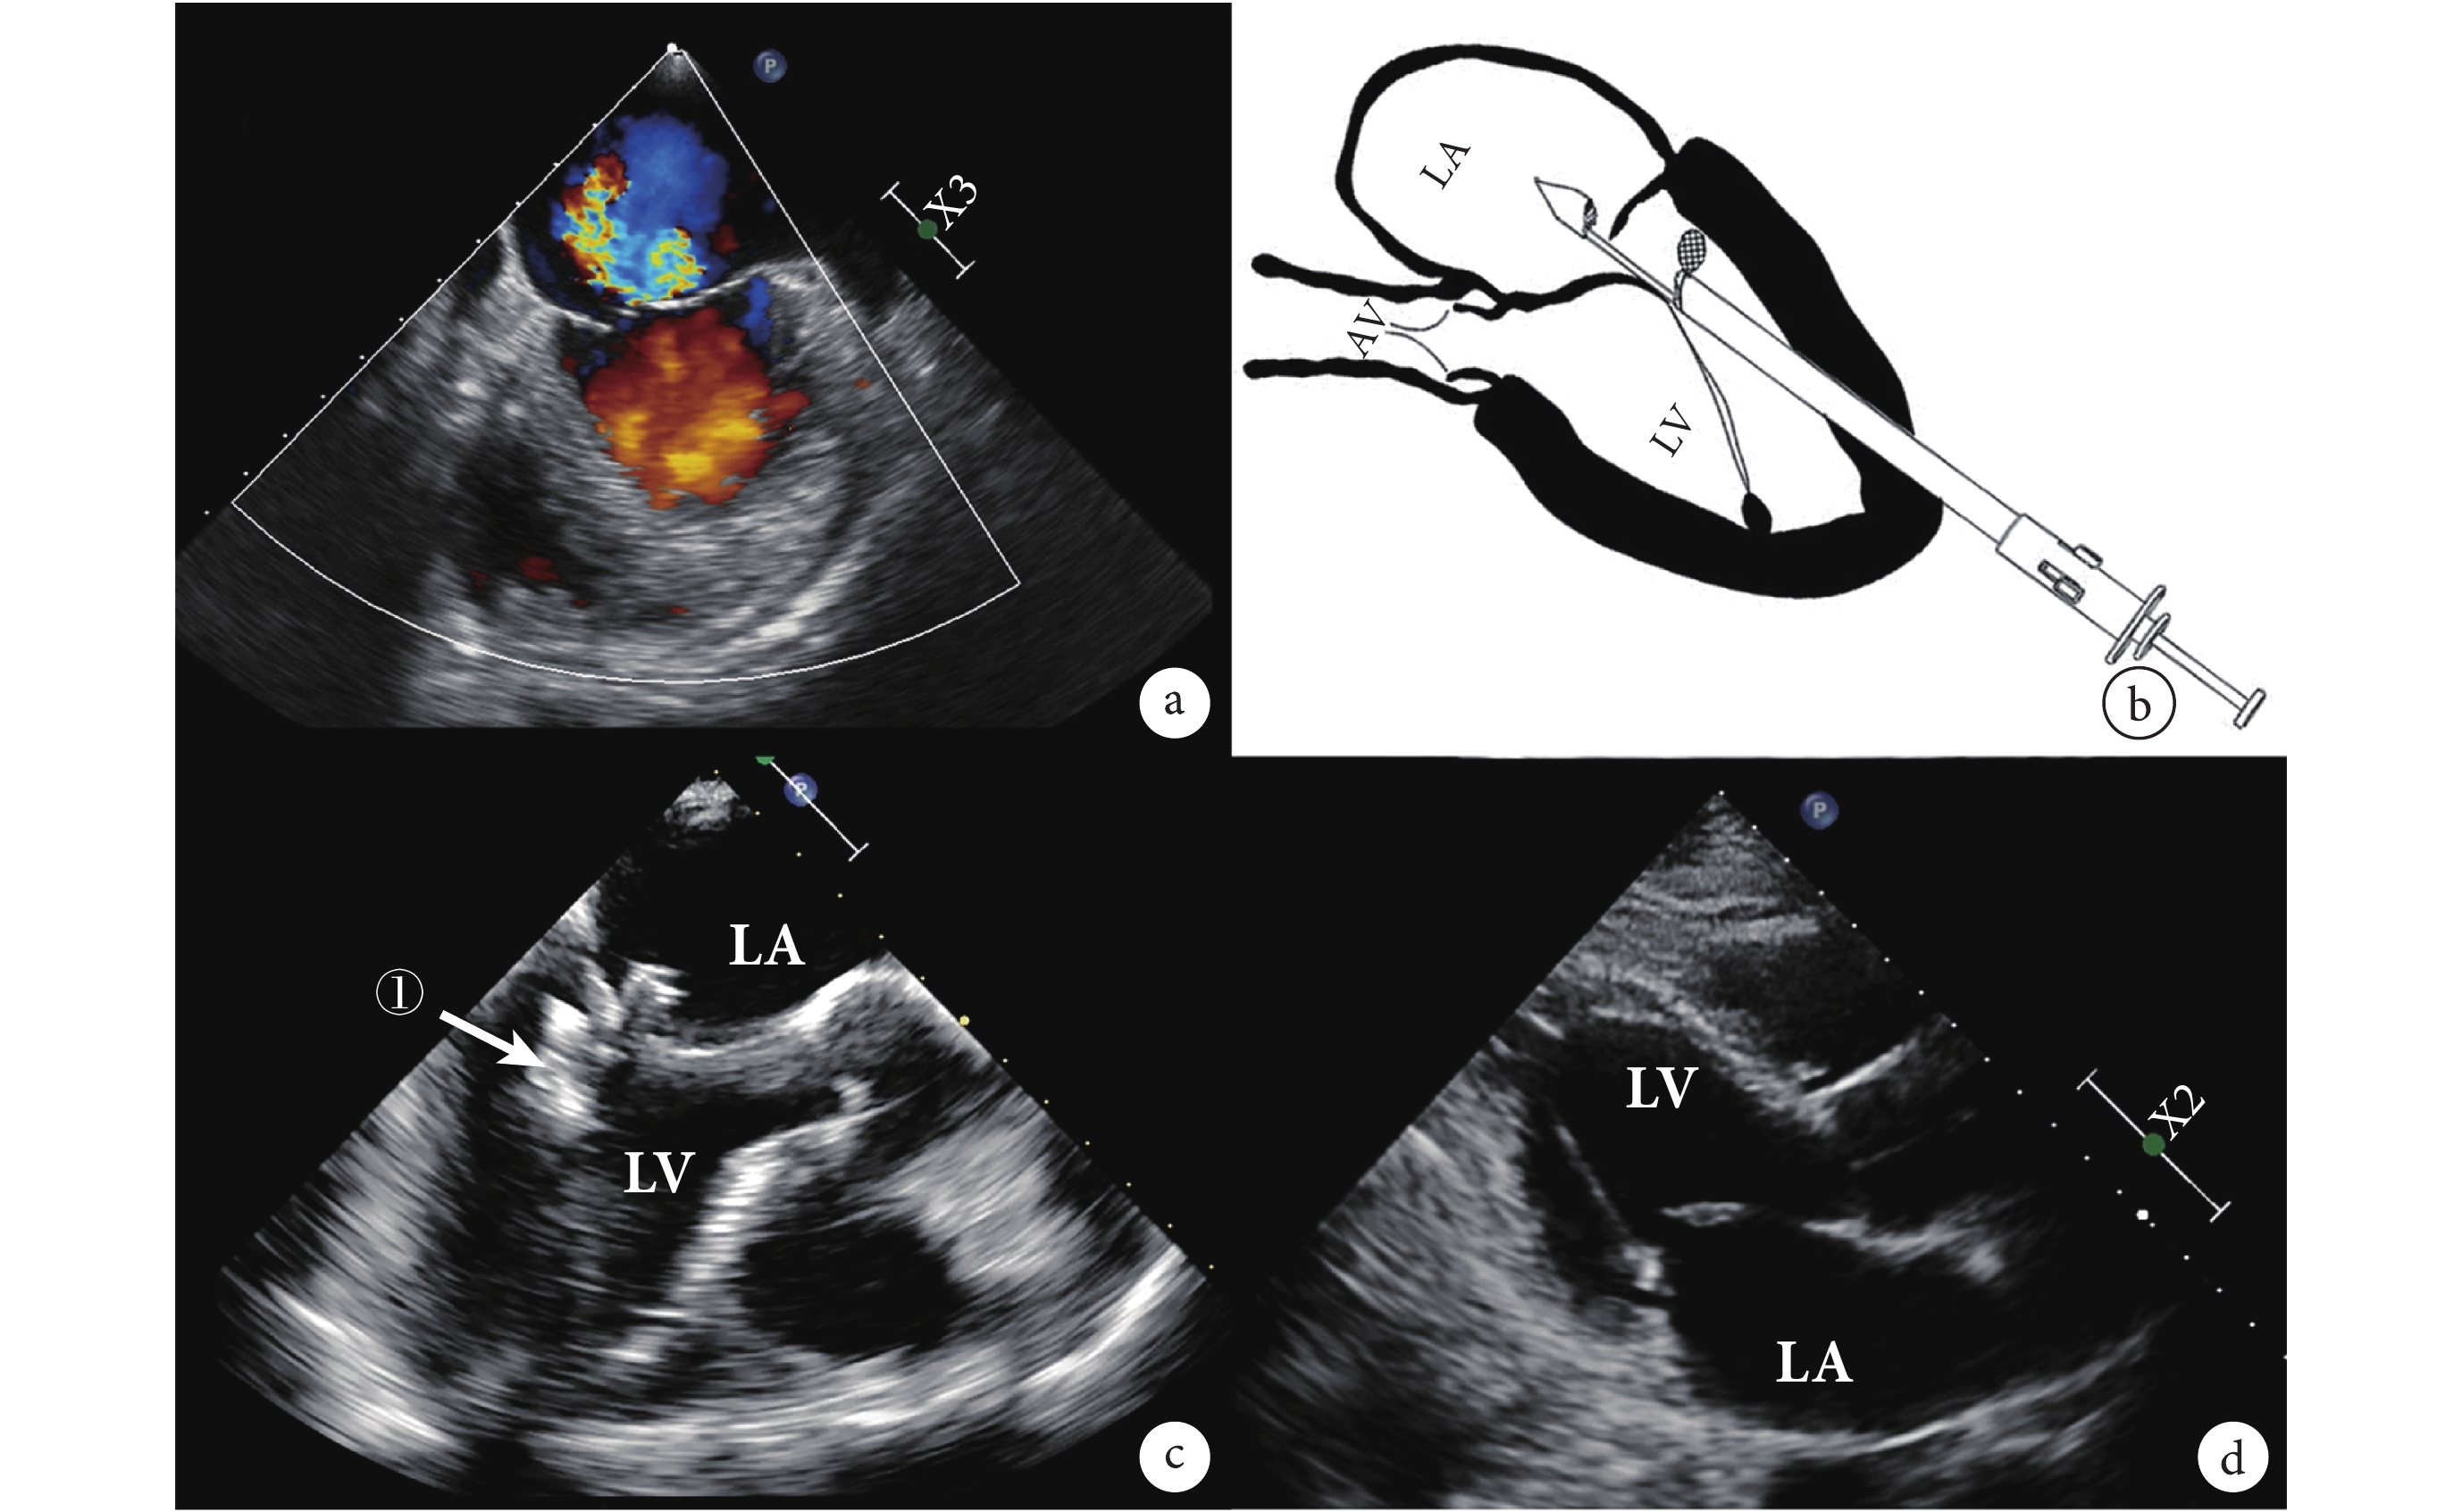

a:瓣膜縫合器遠端咬合器夾住脫垂的瓣葉;b:MitralstitchTM 系統示意圖;c:術中人工腱索植入超聲心動圖,箭頭處為植入的人工腱索;d:手術完成后超聲心動圖;LA:左心房;LV:左心室